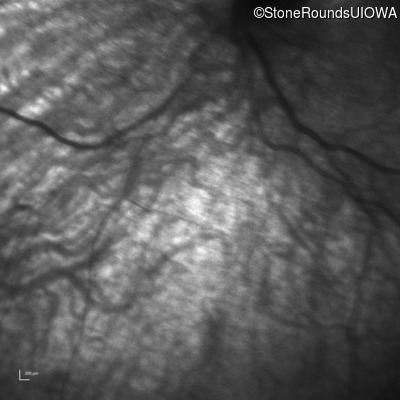

Infrared Fundus Photograph - Right -

No Light Perception

Exemplar

Expanded OCT Stack

×